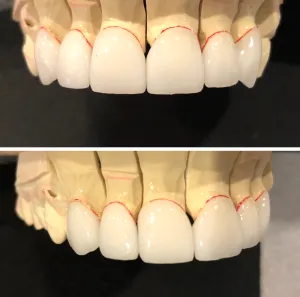

Porcelain Crowns Gallery

These pictures show actual results for patients treated by Dr. Mughal. The photographs have not been altered or retouched.

Before

After

Restoration of discolored, broken, and chipped teeth with porcelain crowns